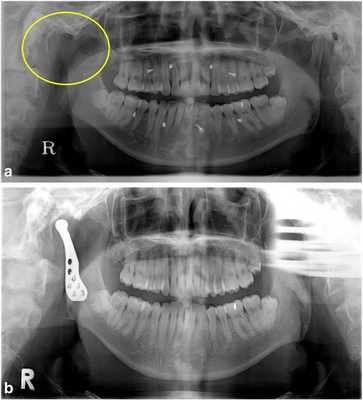

34-летнему мужчине был поставлен диагноз аденоидной кистозной карциномы правого внешнего слухового канала. Ему была проведена операция по удалению карциномы с кондилэктомией правого суставного отростка в отделении отоларингологии (фото 2а). После операции окклюзия стабилизировалась посредством межчелюстных фиксационных винтов и эластичных лент. Ограничений при открытии рта у данного пациента не наблюдалось, однако при открытии рта наблюдалось смещение челюсти в правую сторону. Для поддержки стабильной окклюзии без использования фиксационных межчелюстных винтов через 8 месяцев после первичного вмешательства планировалось провести реконструкцию ВНЧС. После хирургической коррекции сустава межчелюстные винты были удалены, а у пациента было подтверждено стабильное состояние межчелюстного соотношения (фото 2b).

Фото 2.

а) Правый мыщелок был удален (желтый круг) из-за карциномы наружного слухового канала. Для поддержания окклюзии в течение 8 месяцев использовались межчелюстные фиксационные винты и эластичные ленты.

b) Через 1 месяц после реконструкции TMJ фиксационные винты были удалены, а окклюзия оставалась в стабильном состоянии.

Через три месяца в области вмешательства появились болевые ощущения и развилась небольшая припухлость. Несмотря на использование антибиотиков и НПВП, симптомы продолжали сохранятся. Была проведена компьютерная томография (КТ) интересующей области, однако из-за имеющихся артефактов, спровоцированных металлическим протезом, никаких нарушений обнаружить не удалось. Спустя четыре месяца магнитно-резонансная томография (МРТ) помогла диагностировать рецидив опухоли вдоль височной мышцы. В ходе дополнительных операций были удалены и опухоль, и протез, однако у пациента продолжают проявляться рецидивы неопластического поражения в височной области и на участке правого ВНЧС.